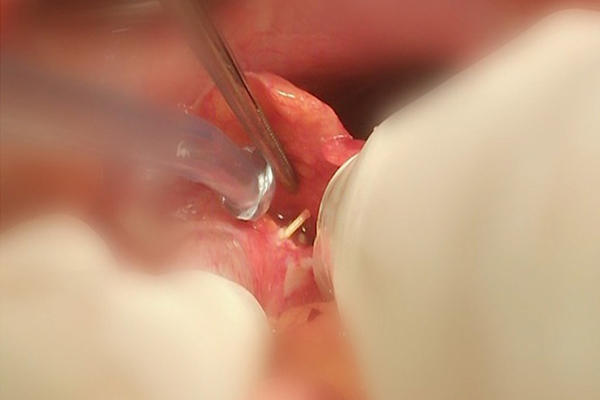

Ăn cháo nấu sẵn, bé 13 tháng tuổi bị mảnh thép rây lọc cháo cắm sâu vào thành họng

- Dị vật cắm sâu vào thành sau họng của cháu bé là 1 đoạn thép mảnh, dài khoảng 2cm từ rây lọc cháo. Mảnh thép này lẫn trong món cháo nấu sẵn gia đình mua ở ngoài.